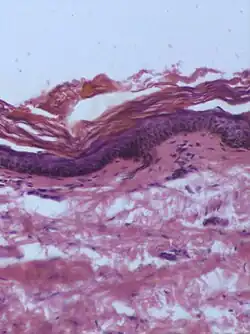

| Intradermal nevus | Within the dermis. | A classic mole or birthmark. It typically appears as an elevated, dome-shaped bump on the surface of the skin.[3][4] |

|

-

Small dermal nevus, with nests of nevus cells (arrows)